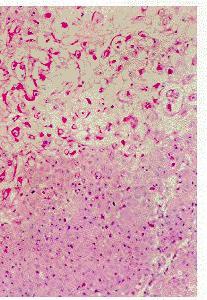

增生性外毛根鞘瘤道病理改變:

(1) 腫瘤組織境界清楚;

(2)為大小不一、形態不一的鱗狀上皮團塊,周邊細胞呈柵欄狀排列,外有玻璃樣膜;(3)腫瘤上皮團塊內可發生囊腔,內有無定形角質;

(4)腫瘤細胞有程度不同的異型性,可出現鱗狀渦。

此瘤位於真皮或皮下組織,邊界清楚,可與表皮相連,呈分葉狀、實質性、囊狀或蜂窩狀。腫瘤由外毛根鞘細胞組成,周邊基底樣細胞呈柵狀排列。外周為PAS陽性的增厚玻璃膜,腫瘤團塊中央可形成囊腔,內含無定型角質及小的鈣化灶。有時瘤團內可見鱗狀鏇渦、表皮樣角化及角珠。瘤細胞可有不同程度的異型及個別角化。惡性增生性外毛根鞘瘤的細胞異型明顯,可侵入周圍組織。